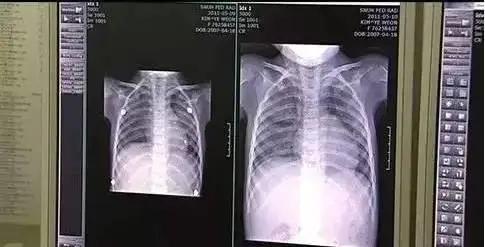

在动物毒性吸入实验中 , 两组吸入不同杀菌剂的老鼠肺部在一个月后出现异常变化 , 与不明原因肺病患者的肺部变化明显一致 。

毒性实验的病理学结果表明 , 含有PHMG等四种有毒成分的杀菌剂 , 在特定条件下 , 能导致肺细胞损伤 。